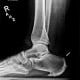

An x-ray of her right foot and ankle at six weeks demonstrated screw fixation and healed osteotomy of the calcaneus (Figure 2). At two months, Mrs. M began physical therapy, and with continued improvement returned to full-time work at five months.